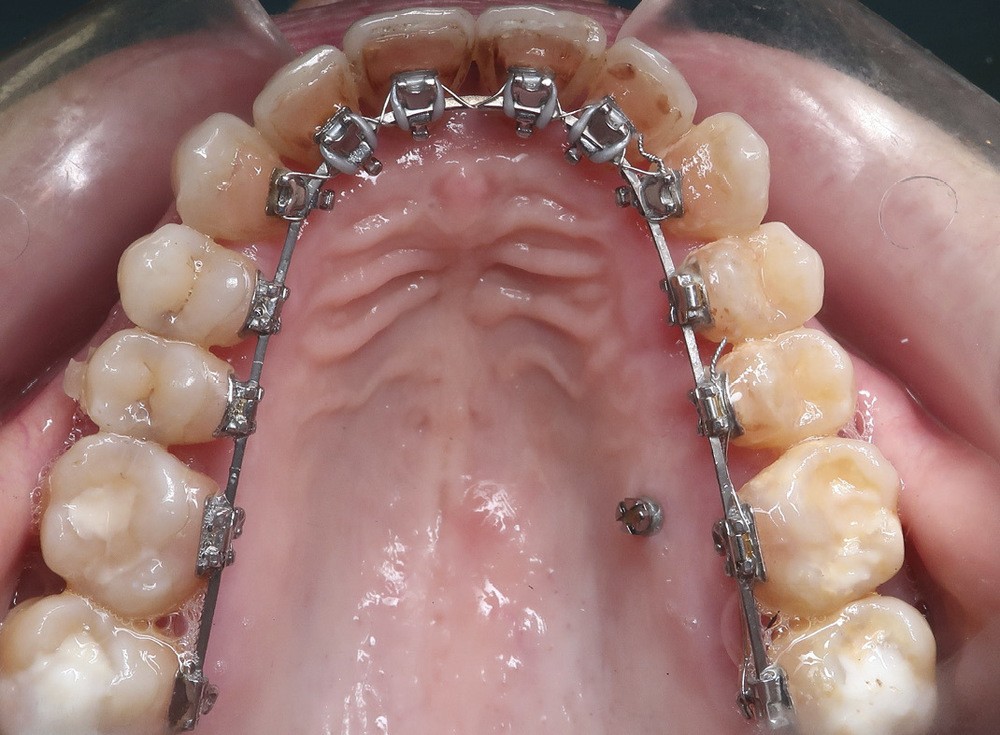

d. Vue occlusale maxillaire durant le traitement orthodontique avec brackets linguales répondant à la demande esthétique du patient.

Les attaches, qu’elles soient vestibulaires ou linguales, ont largement fait leurs preuves quelle que soit la malocclusion à traiter. Grâce aux « mini-attaches », le lingual offre aujourd’hui un maximum de confort pour le patient.

La durée d’un traitement orthodontique réalisé avec des brackets linguales ou vestibulaires est équivalente. Sur le plan esthétique, la technique linguale est la seule parfaitement invisible.